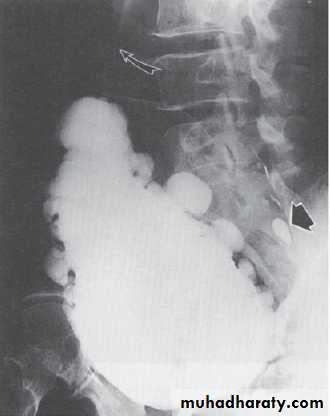

Imaging

Imaging is most important in pts with risk factors for upper tract compromise:

DSD: particularly males who void reflexively

Impaired bladder compliance

Renal US: to screen for calculus, HN, or mass

KUB: radio-opaque calculi

Excretory urography:

Delayed excretion of contrast with high urinary-storage pressures

HUN: marked elevation of intravesical pressure (ie, NDO/DSD) or calculi

VCUG: for VUR, urethral abnormaity